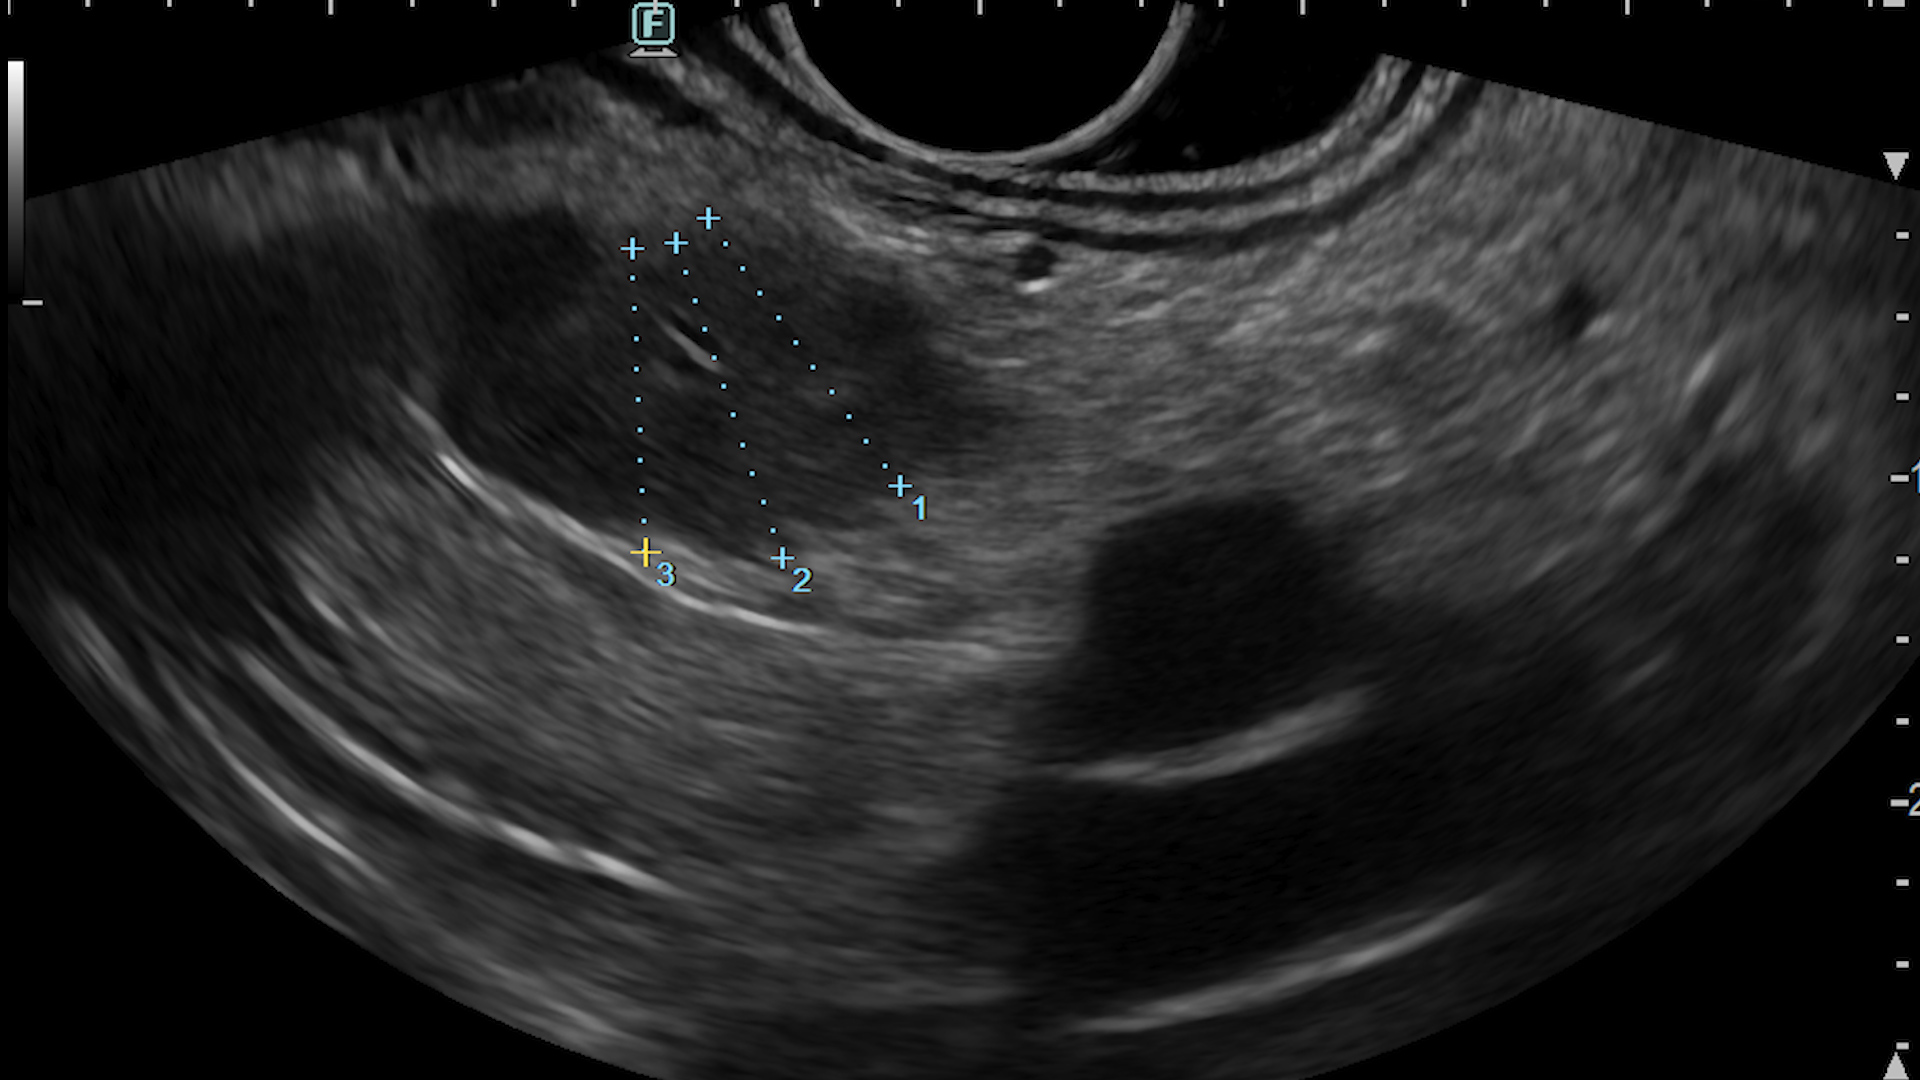

Consequently, an endoscopic ultrasound examination was carried out with tissue acquisition from the mass using a 22G Franssen-type needle (Acquire, Boston Scientific). The tumor was hypervascular on both color Doppler (Fig. 3a), detective flow imaging (Fig. 3b) and contrast-enhanced harmonic imaging (CHI) endoscopic ultrasound (Fig. 4). Histopathology was conclusive for a well-differentiated G1 neuroendocrine tumor, while immunohistochemistry confirmed the diagnosis, showing a Ki 67 index of 1%.